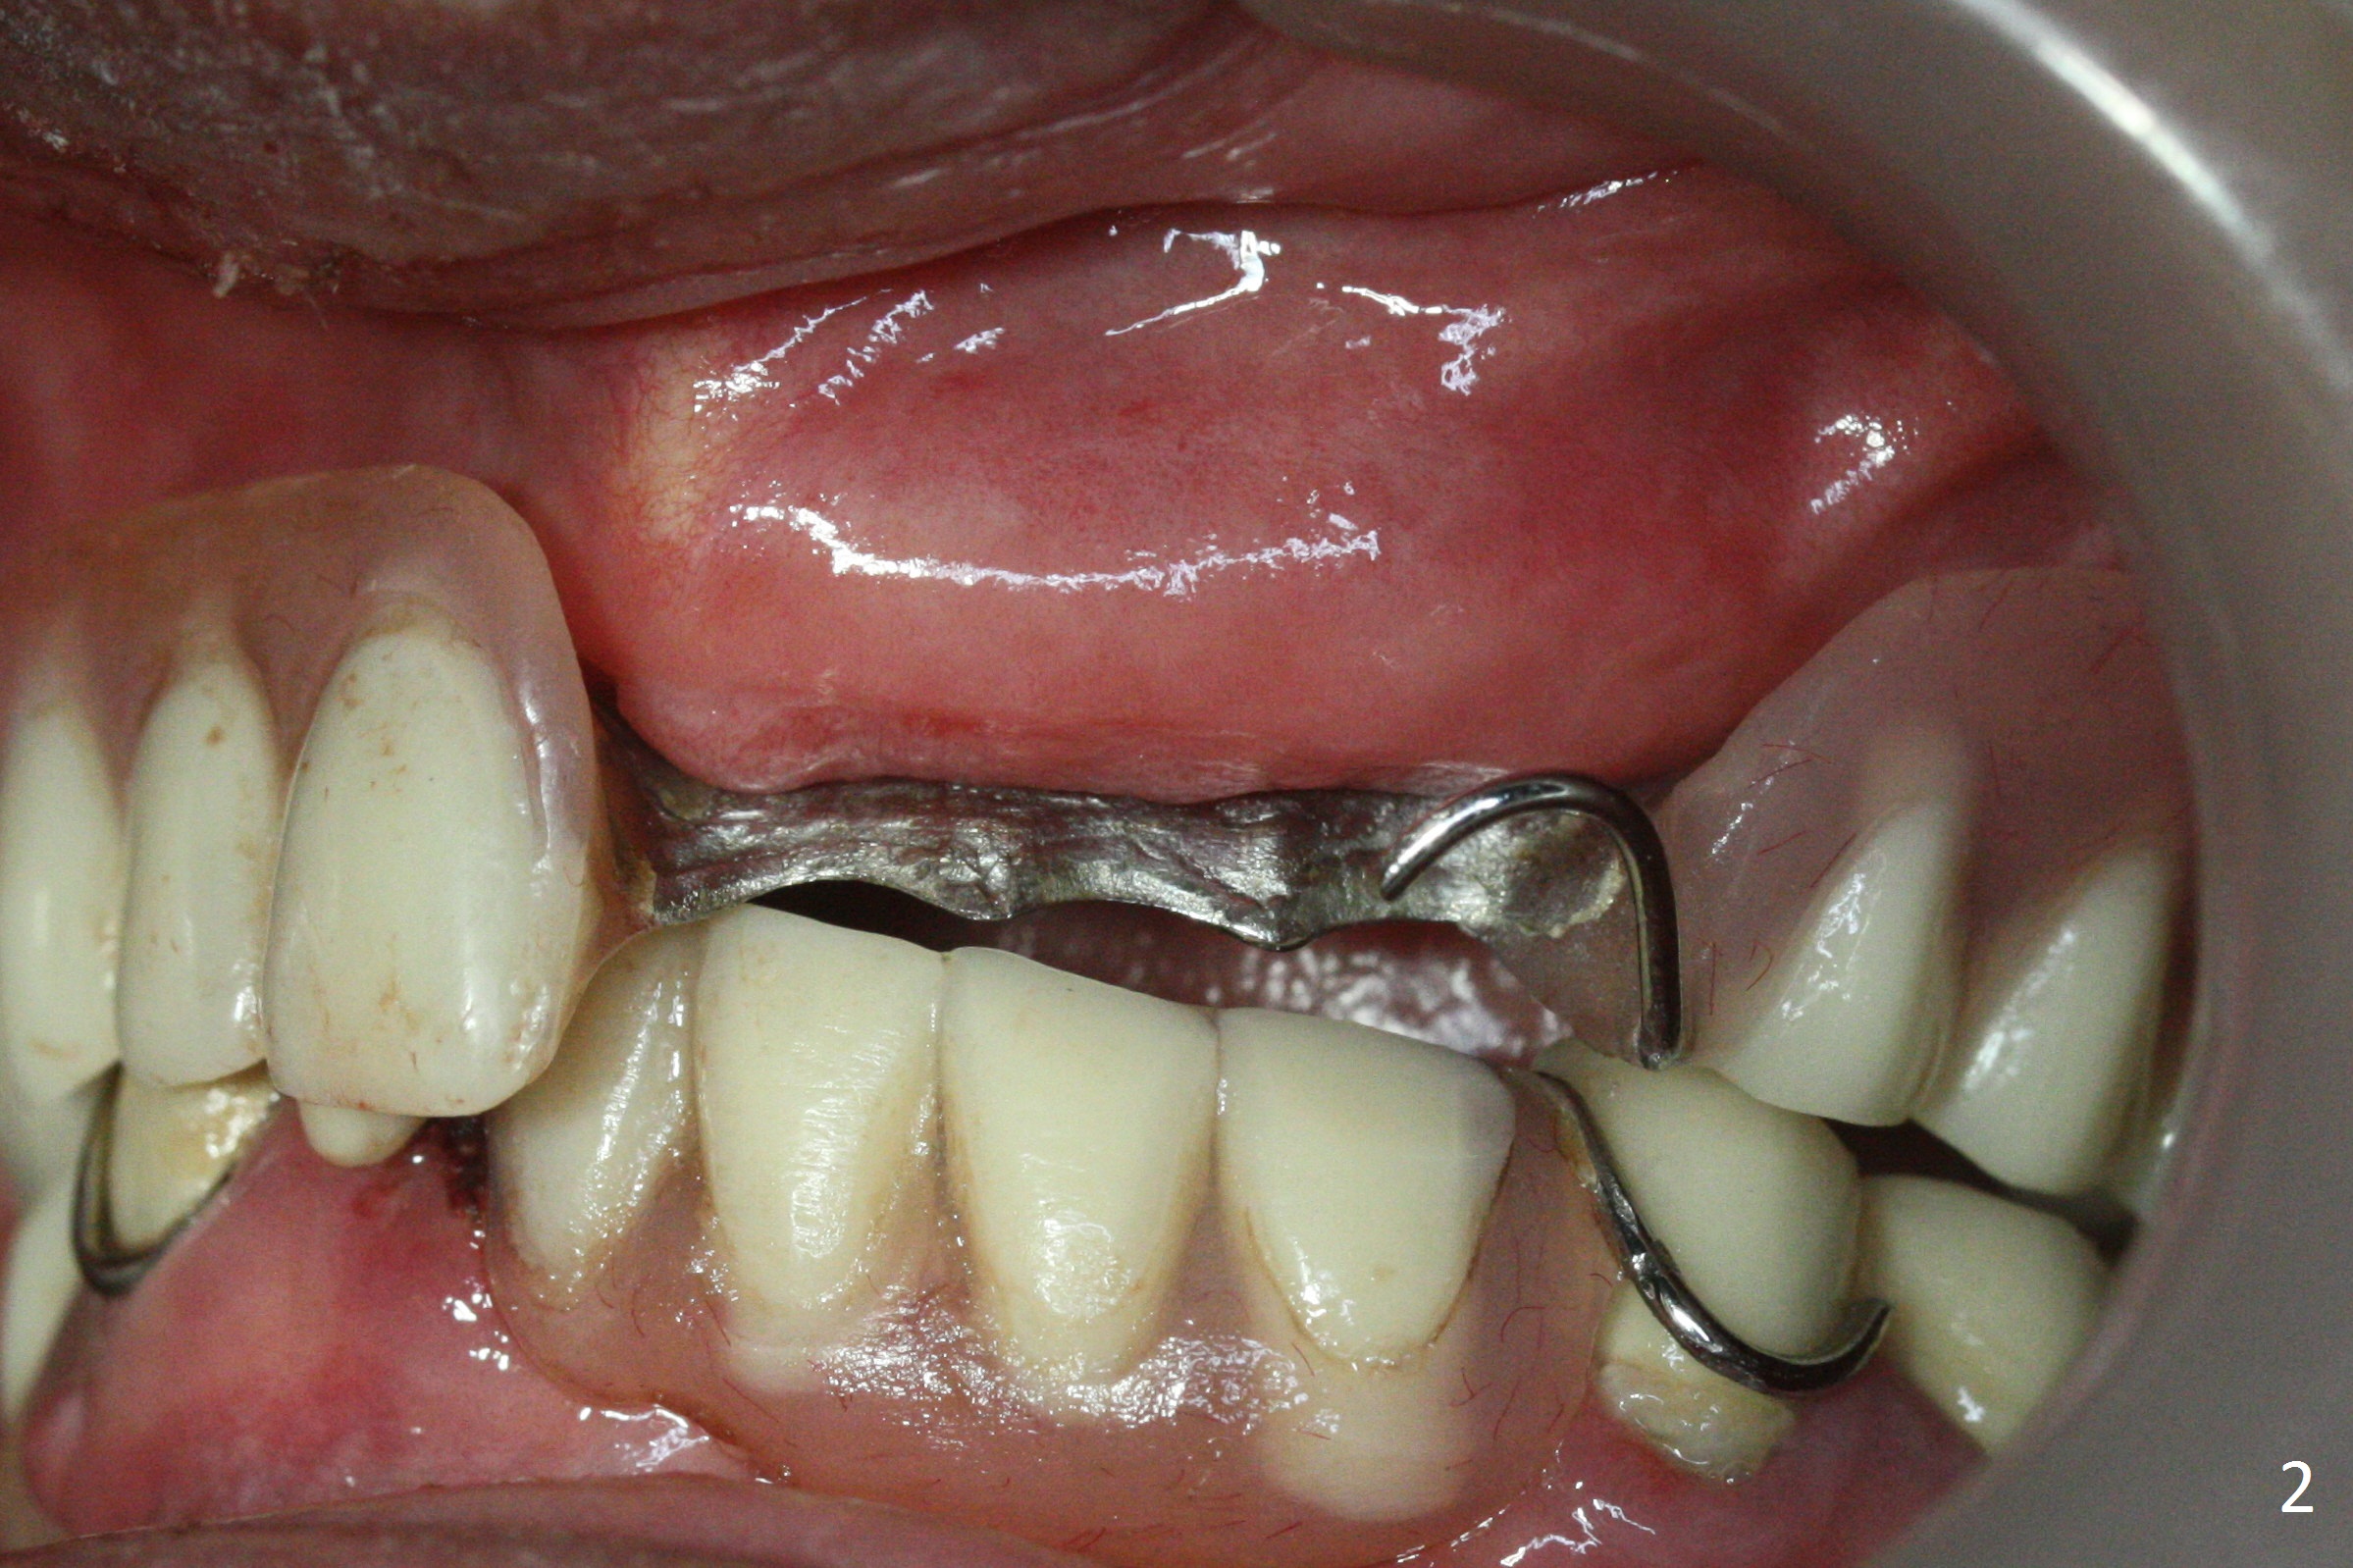

A 62-year-old woman has poor dentition (Fig.1). The most critical area is the upper left anterior: #9-11, which were extracted 4 months earlier (Fig.2). Implants will be placed at #9 and 11 with fabrication of a provisional bridge (Fig.3). After incision, use Magic Split to start bone expansion, followed by micro-osteotomes 1 and 1.5 mm and Magic Osteotomes 3 and 3.8 mm. If the transition between 1.5 and 3 mm osteotomes is not smooth, apply RT2. Place the smallest bone-level implants (for hybrid denture in the future) with gold coated abutments. There should be no interference with or without the partials and in and out. Next step should be removing splinted crowns at #26 and 27 (Fig.1), RCT for #27 and immediate implant at #26 (Fig.5,6 Metronidazole). In fact the splinted crowns at #26 and 27 were lost last week. The patient thinks that she needs 2 implants. The next one is to remove the crown at #5 for RCT (Fig.4).